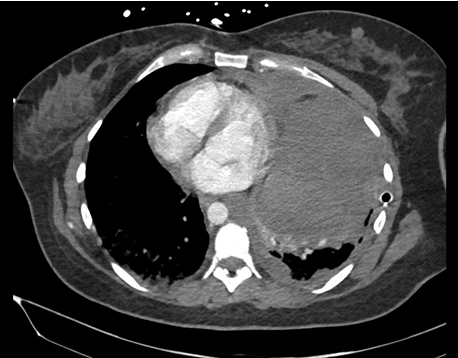

On the first day of hospital presentation, imaging in the ED included chest radiograph (CXR) (Figure 1) and computed tomography (CT) (Figure 2). Imaging revealed a mediastinal mass measuring 10 × 12 × 15 cm with a heterogeneous composition, along with a severe tension hydrothorax and mediastinal shift to the right with a massive left-sided pleural effusion.

Figure 1: Posteroanterior (PA) chest radiograph (CXR) imaging upon arrival to the emergency department prior to emergent thoracoscopy. Imaging revealed complete opacification of the left hemithorax that was revealed to be a mediastinal mass 10 × 12 × 15 cm with heterogenous composition and a severe tension hydrothorax with massive left-sided pleural effusion and severe mediastinal shift to the right.